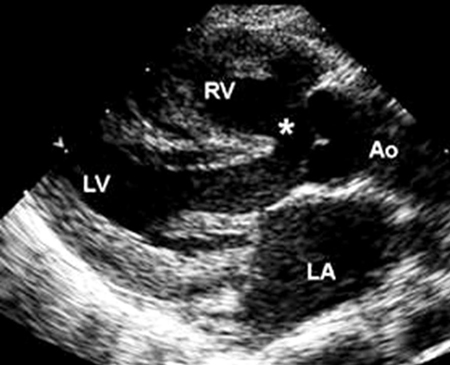

A tetralogia de Fallot é a CC cianótica mais comum, representando 4% a 8% de todos os defeitos, e pode ocorrer como uma lesão cardíaca solitária ou como parte de uma síndrome genética, a mais comum das quais é a síndrome de DiGeorge (uma microdeleção de 22q11.2 ).[40] Ela consiste em 4 anormalidades: defeito do septo ventricular (DSV) de saída, obstrução da via de saída do ventrículo direito (VSVD), uma aorta que se sobrepõe à crista septal ventricular e hipertrofia do VD, um resultado da obstrução da VSVD.[Figure caption and citation for the preceding image starts]: Imagem de ecocardiografia do eixo paraesternal longo em um paciente com tetralogia de Fallot. A aorta (Ao) sobrepõe-se ao defeito do septo ventricular (DSV) (*). (AE) átrio esquerdo; (VD) ventrículo direito; (VE) ventrículo esquerdoImagem cedida por Patrick W. O'Leary, MD [Citation ends].